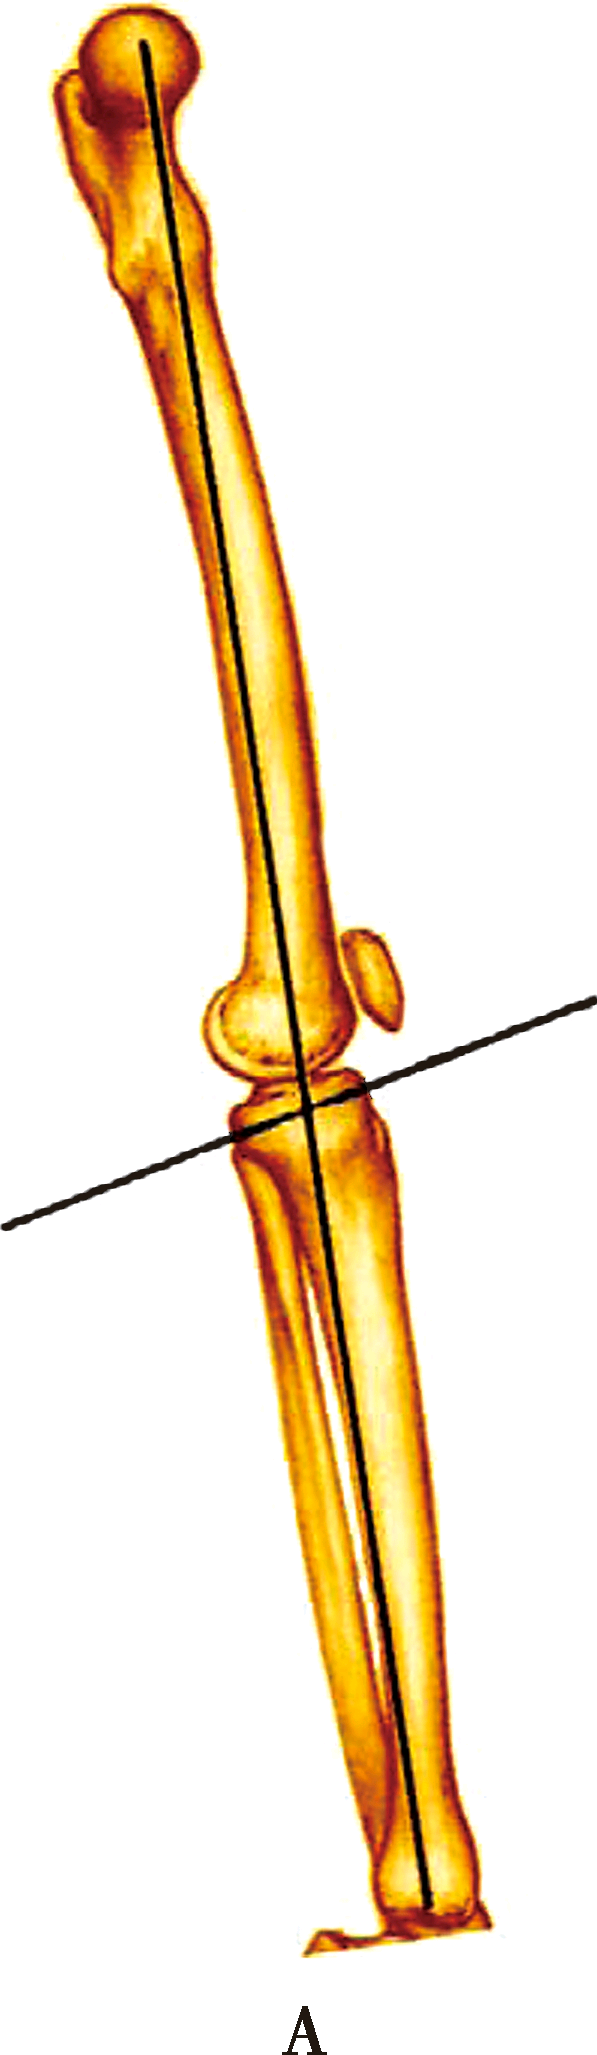

下肢矢状面对线上

A下肢的力线:经过股骨头中心和踝关节中心的连线,该线经过膝关节中心

B胫骨关节面内侧后倾平均约12°

C外侧关节面后倾平均约7°

在矢状面上,下肢的力线是经过股骨头中心和踝关节中心的连线,该线经过膝关节中心。胫骨关节面与力线有平均10°的后倾,由于胫骨平台关节面内外侧后倾角度不同,内侧后倾平均约12°,外侧关节面后倾平均约7°